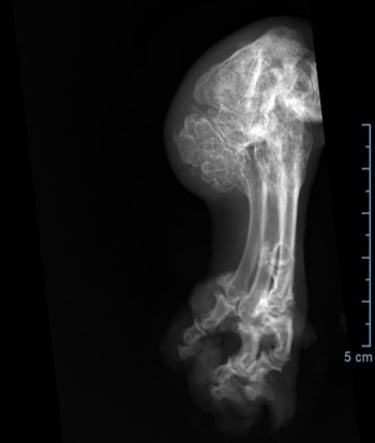

Radiografie (RX)

Een RX is geschikt om botbreuken, een longontsteking, de hartgrootte, arthrose,....op te sporen.

Als de hond - kat niet lang genoeg stil kan blijven liggen dan is een verdoving noodzakelijk. Voor RX van het heupgewricht is een volledige verdoving noodzakelijk.